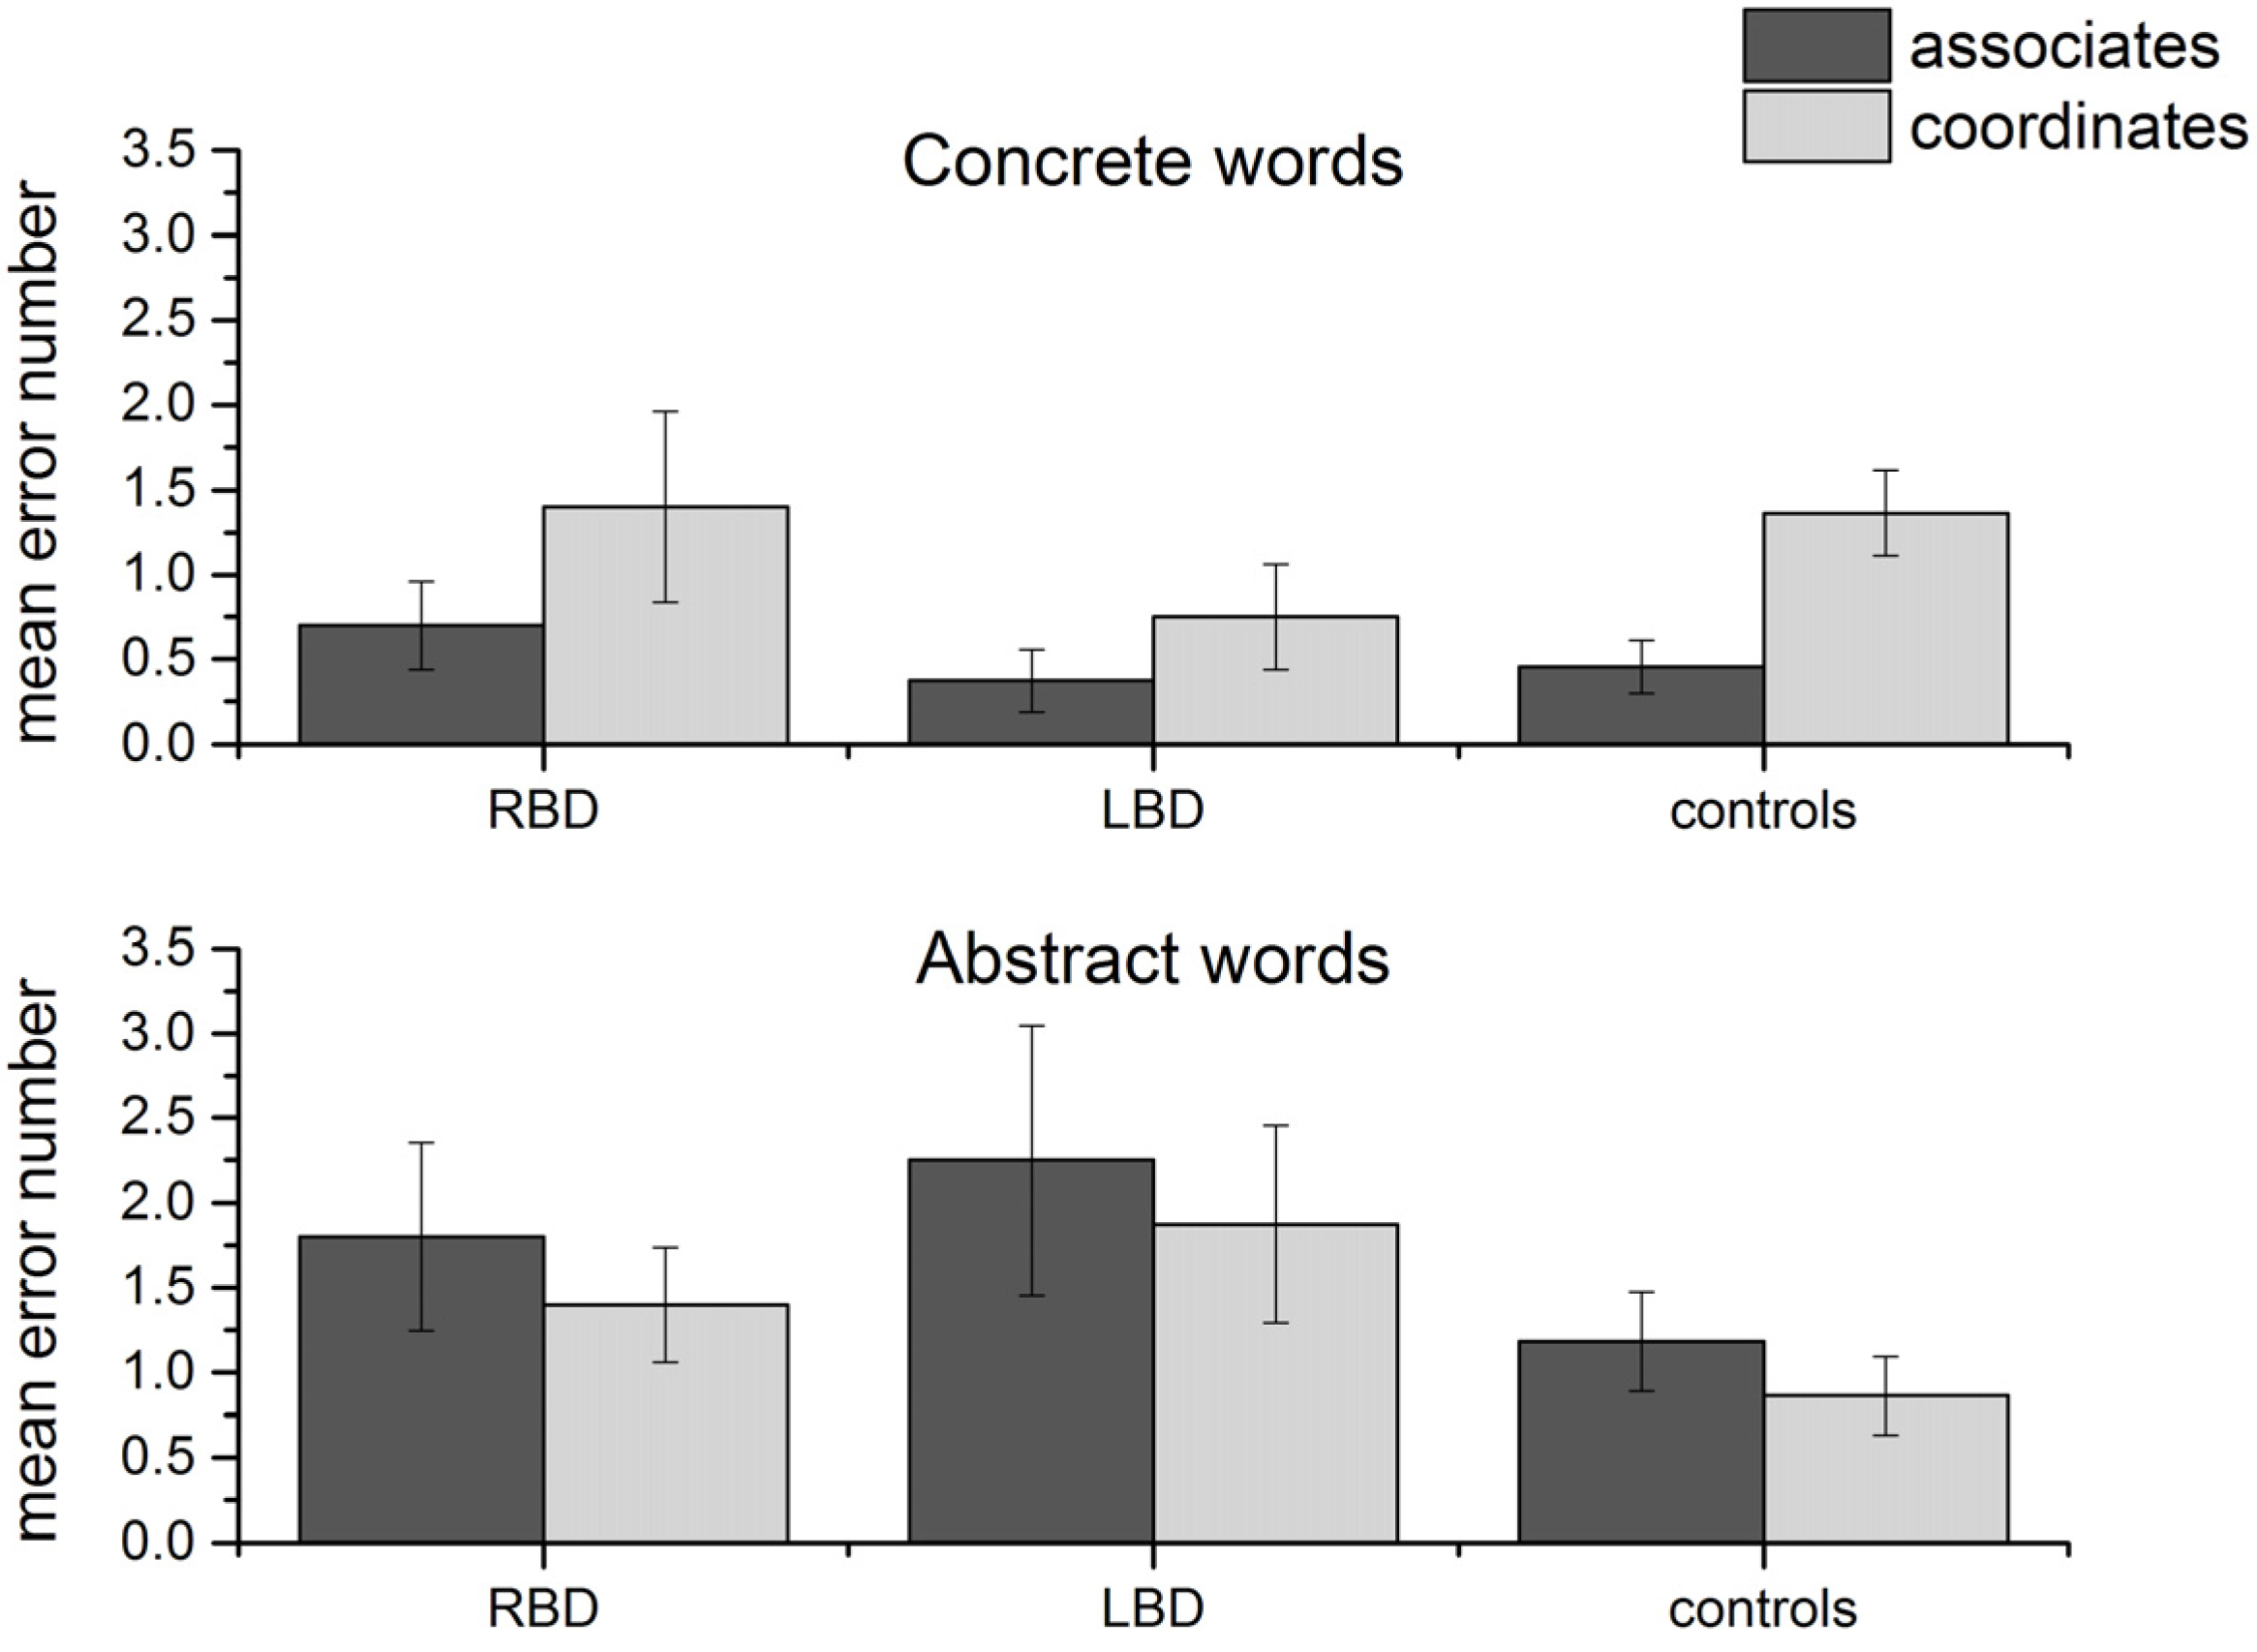

After having verified that performance was lower for left temporal patients with abstract words, we checked whether error type differed depending on the type of item. Indeed, since the target word for each triplet could be an associate or a coordinate word, the second hypothesis was that with abstract words, errors would mainly affect associate rather than coordinate targets, while the opposite should be true for concrete words (following [

13]). An ANOVA on number of errors word type (two levels: abstract and concrete) × semantic relation (two levels: associate

vs. coordinate) × group (three levels: RBD, LBD, controls) showed a significant interaction word type × semantic relation [

F(1, 37) = 7.89,

p = 0.008, partial eta square = 0.18], while the three-way interaction (word type × semantic relation × group) was not significant (see

Figure 2). This is not surprising since we did not expect an effect of left

vs. right lesion

vs. normal brain on the primary organization of concepts.

Post-hoc analyses showed that there were significantly more errors with semantically coordinate compared to associate targets in the case of concrete words (

p = 0.01), while the opposite was true for abstract words, although the results did not reach significance.

Figure 2.

Number of errors for coordinate and associate target words in the three groups. Error bars represent standard errors of the mean.

Figure 2.

Number of errors for coordinate and associate target words in the three groups. Error bars represent standard errors of the mean.